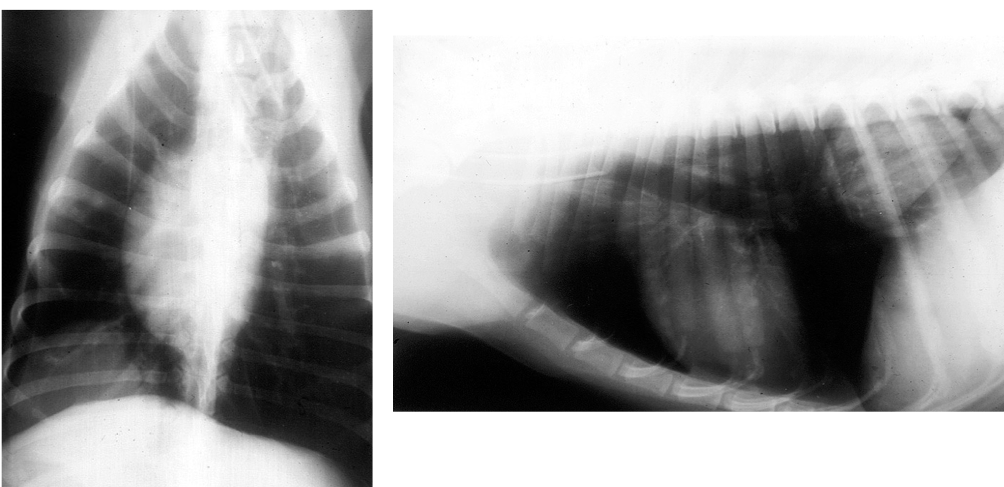

Which lung pattern is shown here?

A

Alveolar pattern

This pattern creates a soft tissue-like opacity within the lungs; think of it as heavy fog obscuring structures.

There is border obliteration (we can no longer clearly distinguish the cardiac silhouette).

We can still see air bronchograms because alveolar diseases spared the airways.